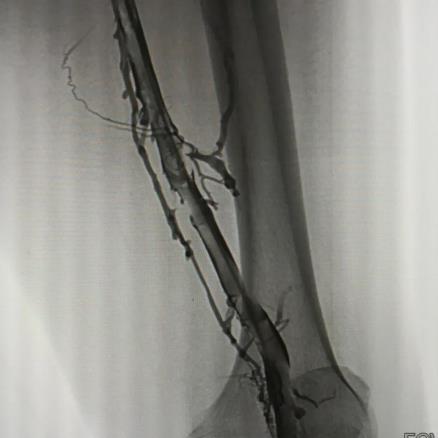

圖解:術前造影見左側股靜脈內大量新鮮血栓,呈明顯“雙軌征”